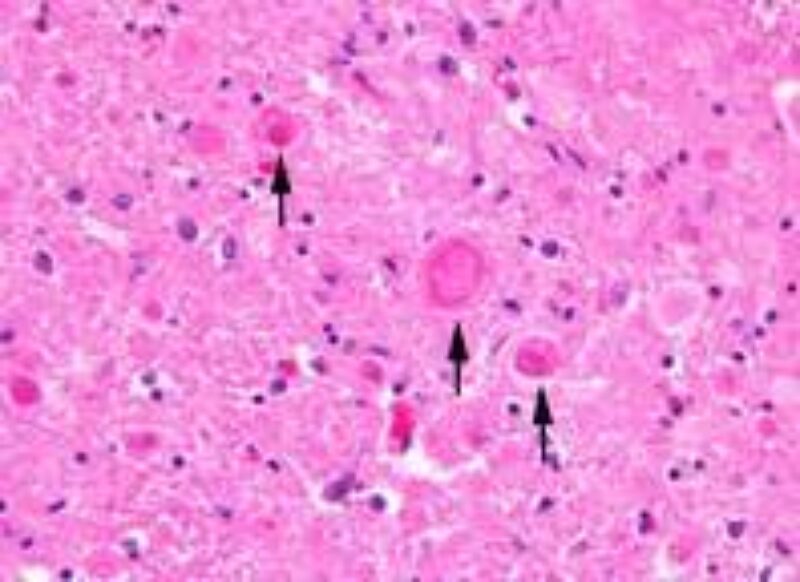

Die Wissenschaftlerinnen und Wissenschaftler untersuchten histologische Proben von vier erkrankten Hunden und entdeckten in der grauen Substanz der Gehirnhälften, dem Kleinhirn, dem Hirnstamm und in den sensorischen Bahnen des Rückenmarks auffällige Ansammlungen. Diese abweichenden Bereiche beinhalteten sogenannte Autophagosomen. Autophagosomen sind Zellbestandteile, die während der Autophagie – dem Abbau von zelleigenem Material – entstehen. Eine Ansammlung von Autophagosomen stört die normalen Abläufe des Nervensystems.